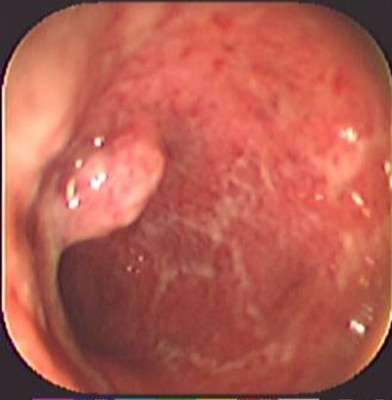

Colitis ulcerosa crónica inespecífica

Envíado por Dr. Carlos Ernesto Arévalo